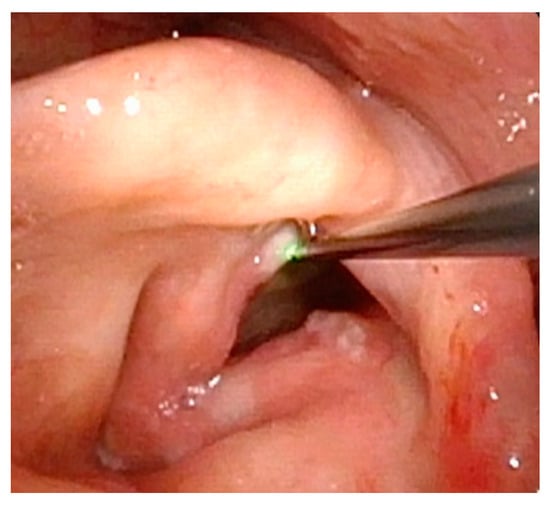

Figure 1 demonstrates a patient who had too aggressive anterior commissure laser treatment. A consequence of this was a very large anterior glottic web. Should this be encountered, the web may be lysed in the midline and steroid-injected (Figure 2). If the web is not the full thickness of the vocal folds, it should be cut with cold steel to help prevent the return of the web during healing. Once healed the web should be significantly improved (Figure 3). Consideration should be given to the dilation of the glottis following lysis.

Figure 2.

One week post-op following laser ablation of laryngeal papilloma and lysis of anterior glottic web.